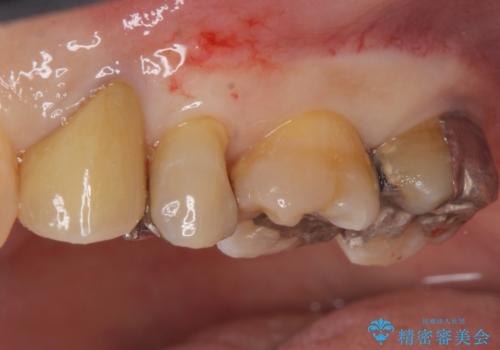

銀歯を除去し隣の歯も虫歯が見られたのでジルコニアクラウン、e-maxインレーで治療を行いました。

適合の良い被せ物、詰め物が入りました。

今後被せ物、詰め物が欠けたりしないようにナイトガードの使用をお勧めしています。